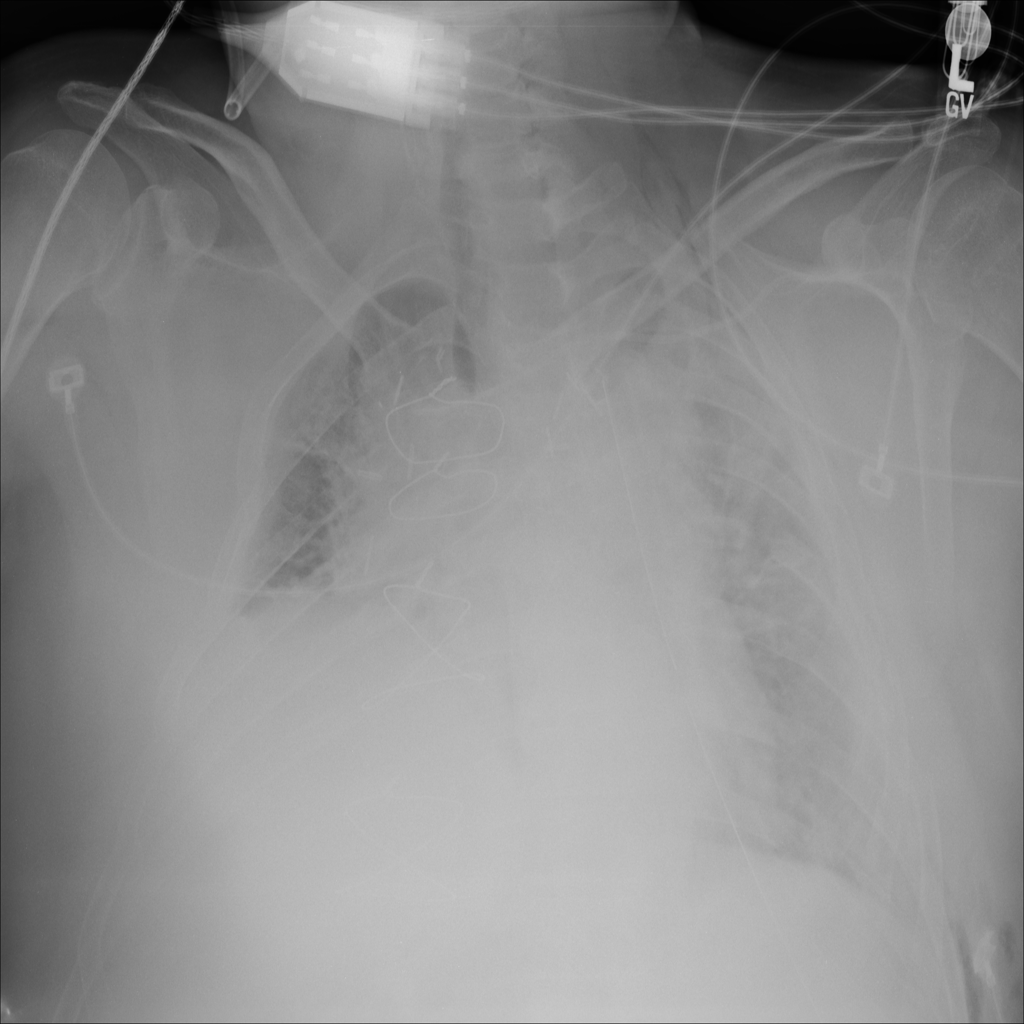

PAT-55FC · IMG-030Emphysema

PAT-55FC · IMG-030

AP